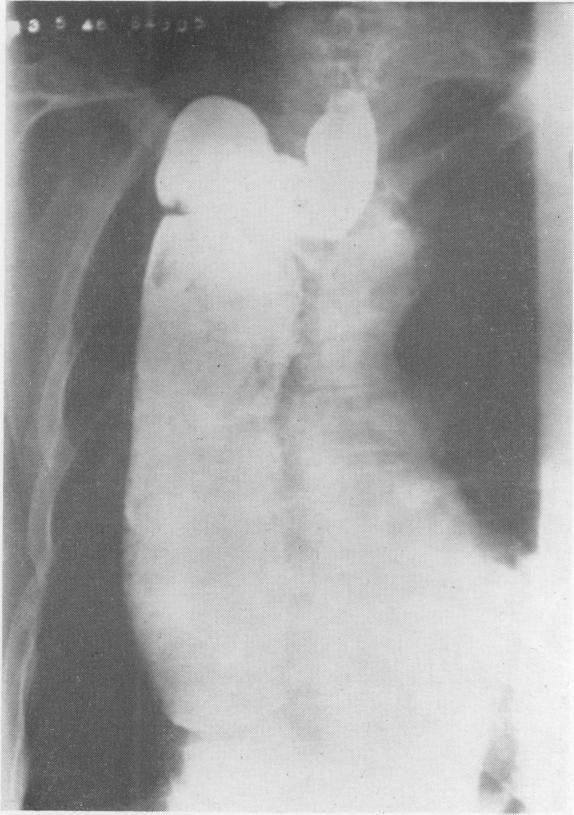

The present position of carcinoma of the oesophagus.

Postgrad Med J. 1947 Mar;23(257):109-39. doi: 10.1136/pgmj.23.257.109.